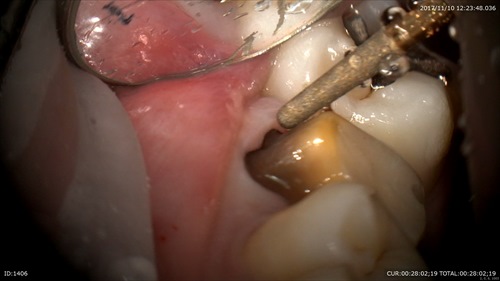

虫歯治療

歯と歯の間に虫歯があります。わかりにくいですよね。

ここです。無痛で行う為のマイクロスコープ。最小限の形成。

早く歯科ドックしてよかったですね。見逃したら神経まで。。。

必ずチェック!!

虫歯用マイクロエキスカで丁寧に。ここを荒く削ると術後痛みます。